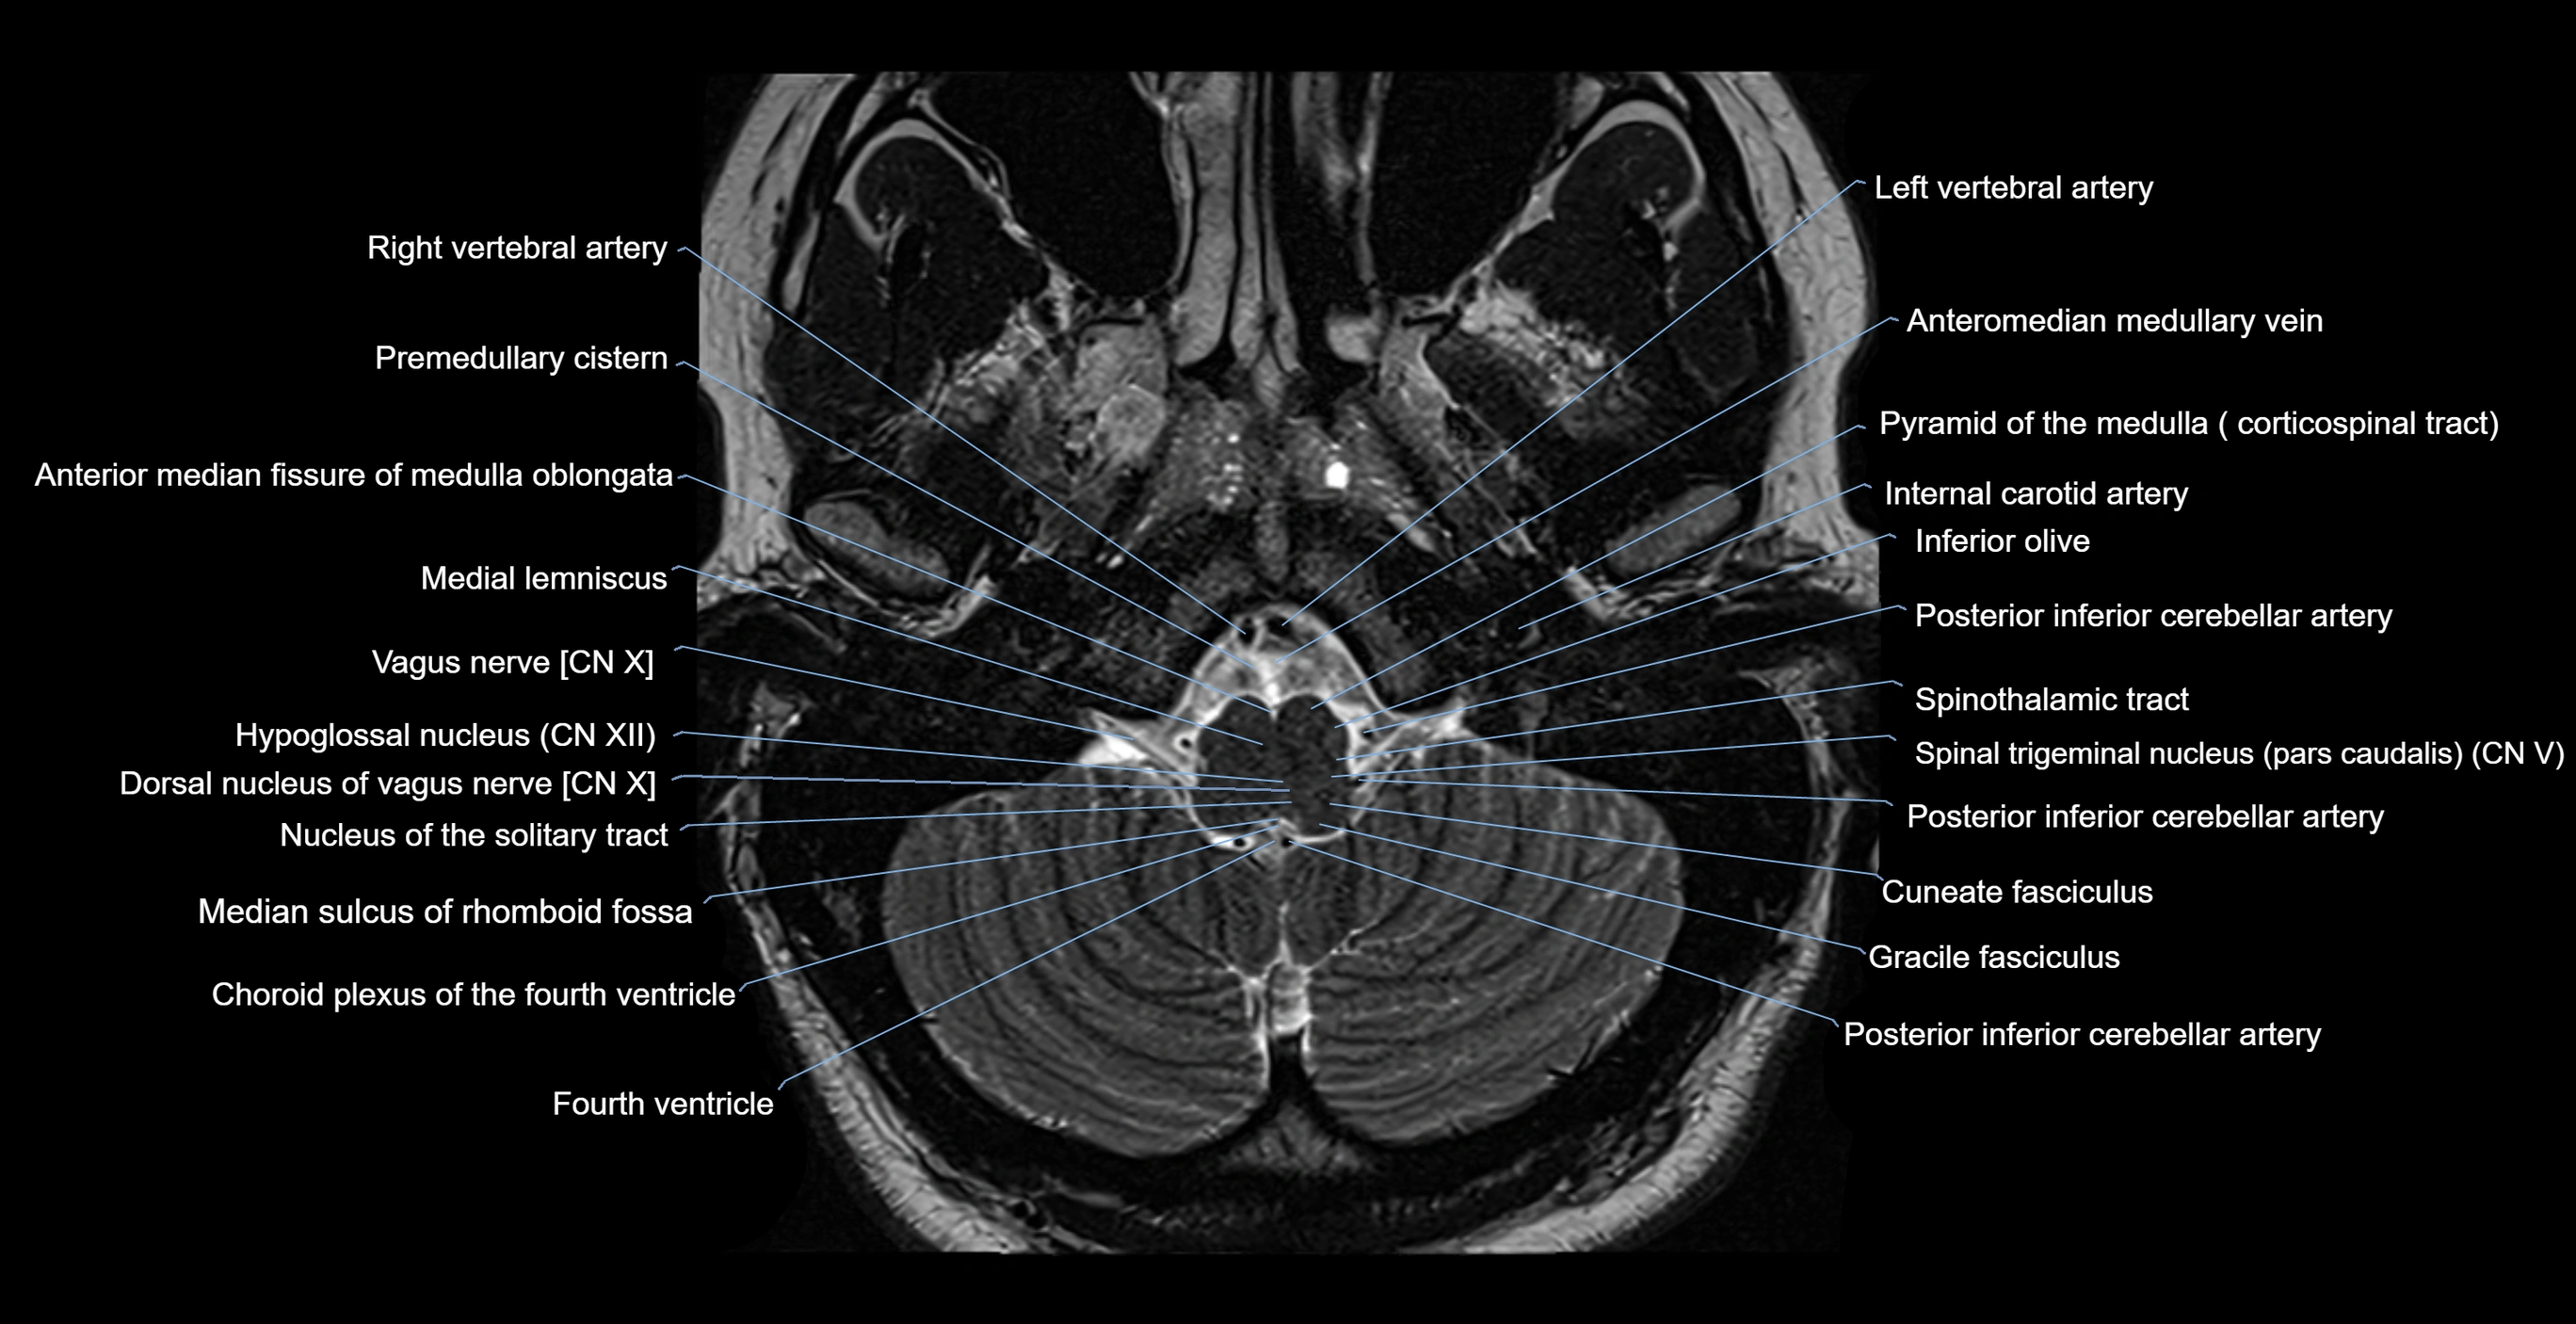

MRI images